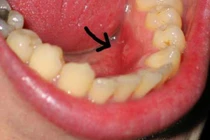

(Kiến Thức) - Hút thuốc lá, nhiễm virus HPV, duy trì chế độ ăn uống nghèo nàn… được xem là những nguyên nhân hàng đầu gây ung thư môi.

Lười vệ sinh răng miệng. Vệ sinh răng miệng kém góp phần tạo ra một môi trường nuôi dưỡng sự phát triển cũng như nhân rộng các vi khuẩn và mycetes, có lợi cho sự hình thành của chất nitrosamine gây ung thư.